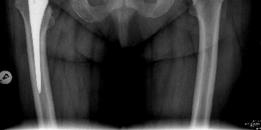

- True Anteroposterior (AP) Pelvis: Standardized view (patient supine, feet internally rotated 15 degrees) to assess joint space, osteophytes, subchondral changes, femoral head migration, bone quality, and pelvic landmarks. Templating for acetabular component size and position is performed.

- Full-length AP Femur: For femoral component templating, but also provides context for overall limb alignment.

Clinical & Radiographic Imaging